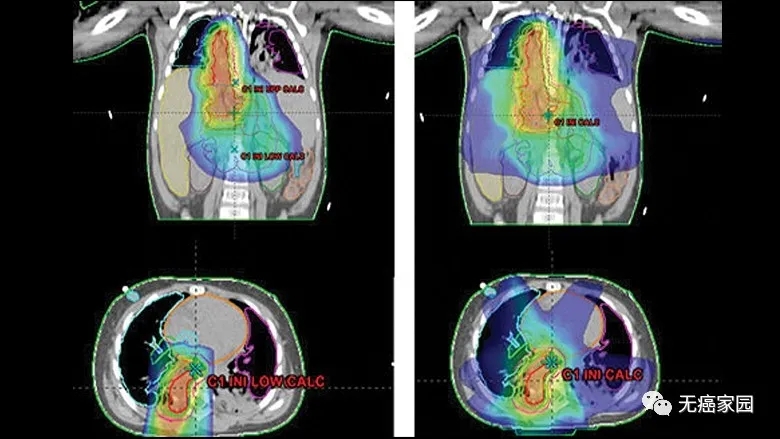

所有患儿在自体干细胞移植治疗后接受质子治疗,26例患儿接受笔形束扫描(PBS)质子治疗,19例接受双散射(DS)质子治疗,其中2例联合X线调强放疗(IMXT);11例患儿接受剂量递增治疗,8例患儿接受转移灶照射。

与X线调强放疗(IMXT)相比,笔形束扫描(PBS)质子治疗具有更优的剂量适形性及靶区覆盖情况。

使用质子(左)与X射线治疗(右) 质子治疗对周围重要器官损伤更少